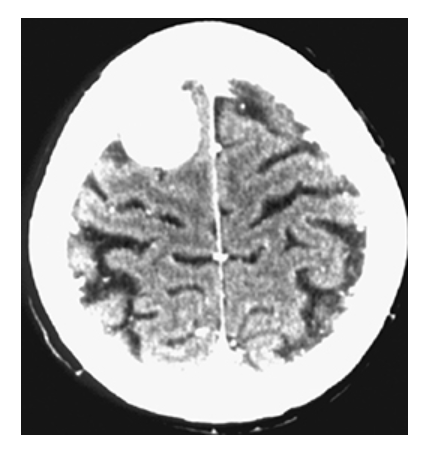

Meningioma. Noncontrast CT shows round, high-density mass over the convexity of the right parietal lobe.

Meningioma. Postcontrast CT image shows a round, markedly contrast-enhancing mass over the convexity of the right parietal lobe.